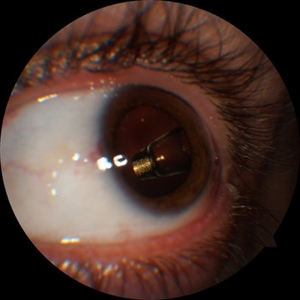

Ozurdex in AC

Apr 1 2025 by Korey Starkey

90-year-old patient with an Ozurdex implant that migrated into the AC and with the cornea decompensating. Patient recommended for urgent surgery to remove implant. Vision OD at this visit was CF @ 2ft, most recent visit vision is 20/400, PH 20/25.

Photographer: Korey Starkey

Imaging device: Topcon

Condition/keywords: anterior chamber, corneal decompensation, external, external photography, Ozurdex implant, Topcon